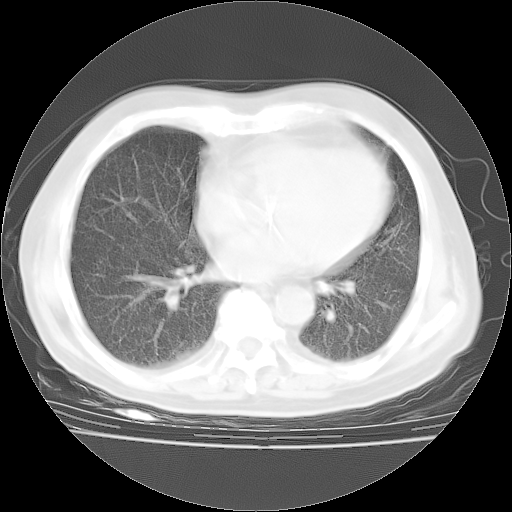

今天部分检查

轻微咳嗽,无痰,(体温正常时)R20次/分,P75次/分,双肺底、腋下可闻及少量捻发音。下肢轻度浮肿。

血常规:白细胞9.11×109/L,N0.92,L5.64,血小板39.2×109/L,HB148g/L,ESR2mm/H。

尿常规:潜血+

血生化:总蛋白69.71g/L,白蛋白38.40g/L,球蛋白31.31g/L,CRP27.9mg/L,尿素氮11.98mmol/L,肌酐106μmol/L,乳酸脱氢酶1099 U/L,肌酸激酶108U/L,CK-MB 61U/L。

腹部B超:胆囊壁增厚,肝、胆、胰、脾、肾无异常,肠系膜淋巴结、腹膜后淋巴结无增大。

ECG:右心室增大

心脏超声检查:无右心室增大。

增加治疗:异烟肼、利福平、乙胺丁醇,静滴左氧氟沙星、参麦注射液。甲强龙从80mg暂减为40mg。

强的松3月1日改为10mg qd,4月1日改为10mg qod。3月份以前的减量过程和环磷酰胺疗程需等明天查看记录(我岳父自己做的记录在他家里)。